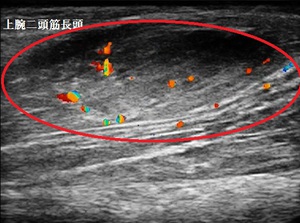

右上腕遠位端 超音波長軸像 同部 4週後

当接骨院で超音波検査を実施したところ、右上腕二頭筋が腫れて炎症が起きている様子がみとめ

られました(左上画像の丸の中=腫れ、炎症=赤、橙、青色の点)。

画像右上は4週後の画像ですが、女性は仕事を休むことなく炎症症状が消失しました(矢印は腫れが

若干残存している状態)。